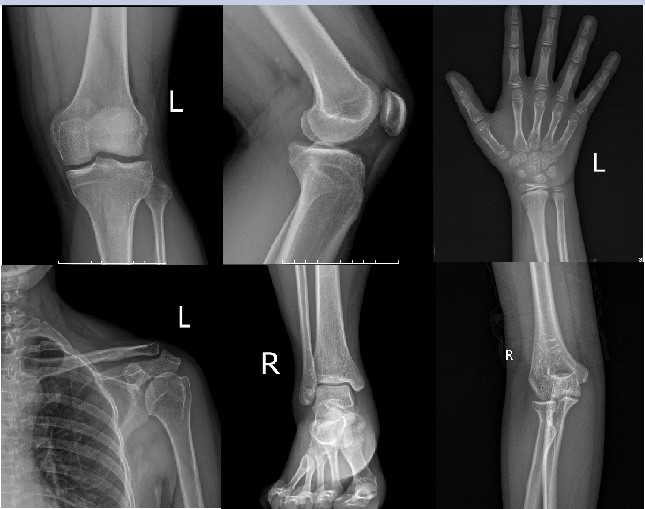

🔬 Làm sao biết xương đã đóng chưa?

✅ Chụp X-quang xương cổ tay, xương đầu gối hoặc xương chậu để kiểm tra.

✅ Nếu sụn tăng trưởng vẫn còn khe hở, vẫn có khả năng cao thêm.

✅ Nếu sụn đã khép hoàn toàn, việc tăng chiều cao sẽ khó khăn hơn nhưng không phải là không thể!